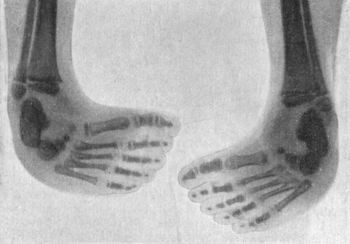

274 143.Radiogram of Bilateral Congenital Club-foot in an Infant

275 144.Congenital Talipes Equino-varus in a Man